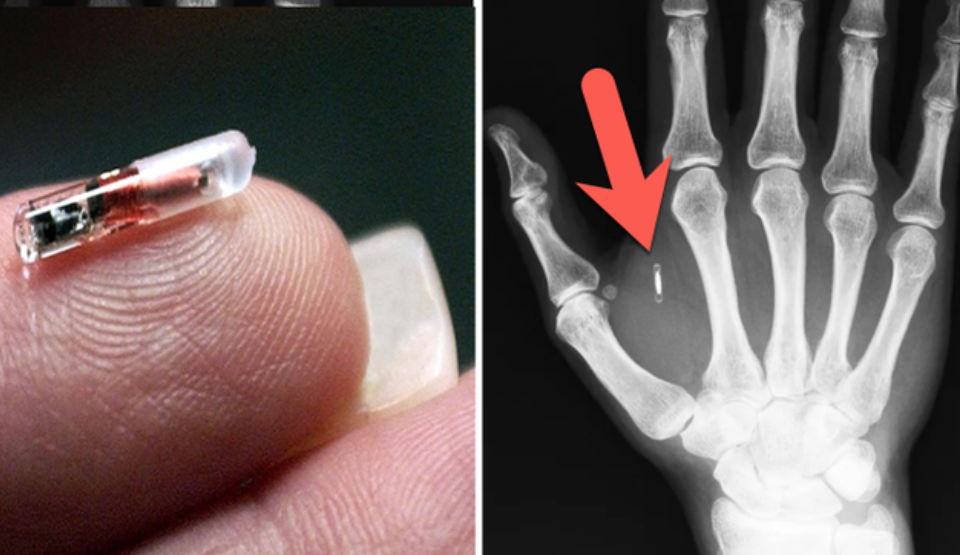

Un magician a uitat parola cipului implantat în propriul corp